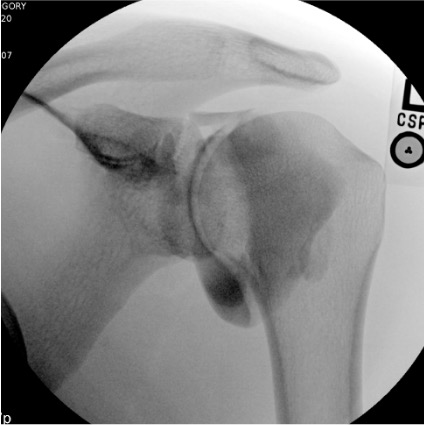

Shoulder

Finding

Fluoroscopic Appearance

Full-thickness rotator cuff tear

Contrast fills the subacromial/subdeltoid bursa = communication with glenohumeral joint through full-thickness tear

Biceps tendon sheath filling

Normal — the long head biceps tendon sheath communicates with the glenohumeral joint

Capsular adhesion (frozen shoulder)

Reduced joint volume; capsule does not distend; obliteration of axillary and subscapularis recesses

Labral tear (SLAP/Bankart)

Not diagnosed on fluoroscopy — MR arthrogram images are diagnostic

Bursal communication (shoulder): absent / present (subacromial = full-thickness RCT)

Shoulder: missing subacromial bursal fill

If evaluating for RCT by arthrogram, upright positioning after injection shows bursal fill better; take fluoroscopic images in multiple positions